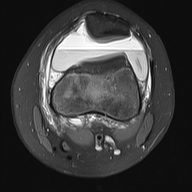

轴位PD序列

脂肪抑制序列

关节内大量积血,可见血细胞比容增高征。股骨外侧髁前部及髌骨内侧可见挫伤性微骨折。髌骨内侧支持带及髌股内侧韧带水肿增厚。髌骨内侧关节面下关节软骨浸润,提示I期骨软骨损伤。

髌骨外侧隐窝可见游离体,其信号强度与关节软骨一致,提示髌骨关节软骨外剥离损伤。股骨滑车和股骨关节软骨正常。

胫骨近端和腓骨骨骺以及股骨远端延伸至干骺端的骨骺周围可见局灶性骨髓水肿。这些提示存在局灶性骨骺周围水肿区。

十字韧带和侧副韧带正常。半月板正常。股四头肌腱和髌腱正常。

该病例具有短暂性髌骨外侧脱位复位损伤的特征性表现,包括预期的骨挫伤模式、内侧髌骨支持带/内侧髌股韧带损伤、髌骨骨软骨损伤以及髌骨软骨游离体。